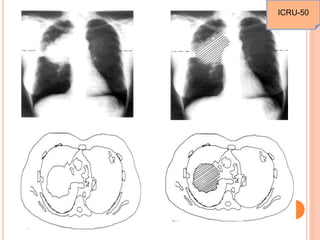

2 field(AP-PA)

3 field

4field(box) Arc